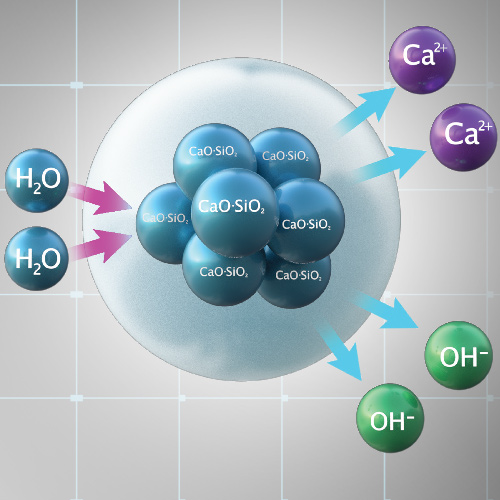

Solving Clinical Challenges With Calcium-Releasing Products

Wednesday, February 19, 2020

Some restorative materials have an exceptional ability to meet the needs of both dentists and patients. For example, calcium-releasing products promote an alkaline environment and apatite formation. Learn how these new materials help meet clinical challenges.

Bioactive Composites for the Clinician and Patient

Tuesday, May 22, 2018

Restorative materials are constantly under biological assault from acid attack and the effects of demineralization. However, bioactive composites respond to changes in pH by releasing and recharging essential minerals to help protect teeth. In this eBook, Dr. Robert Lowe demonstrates the features of...

The New Standard in Cementation: Bioactivity

Friday, April 1, 2016

The long-term success of zirconia restorations depends on prep design, retention, durability, and prevention of microleakage and sensitivity. A new bioceramic luting cement addresses these issues by combining clinical ease-of-use with solid retention and the protective mechanism of bioactivity.